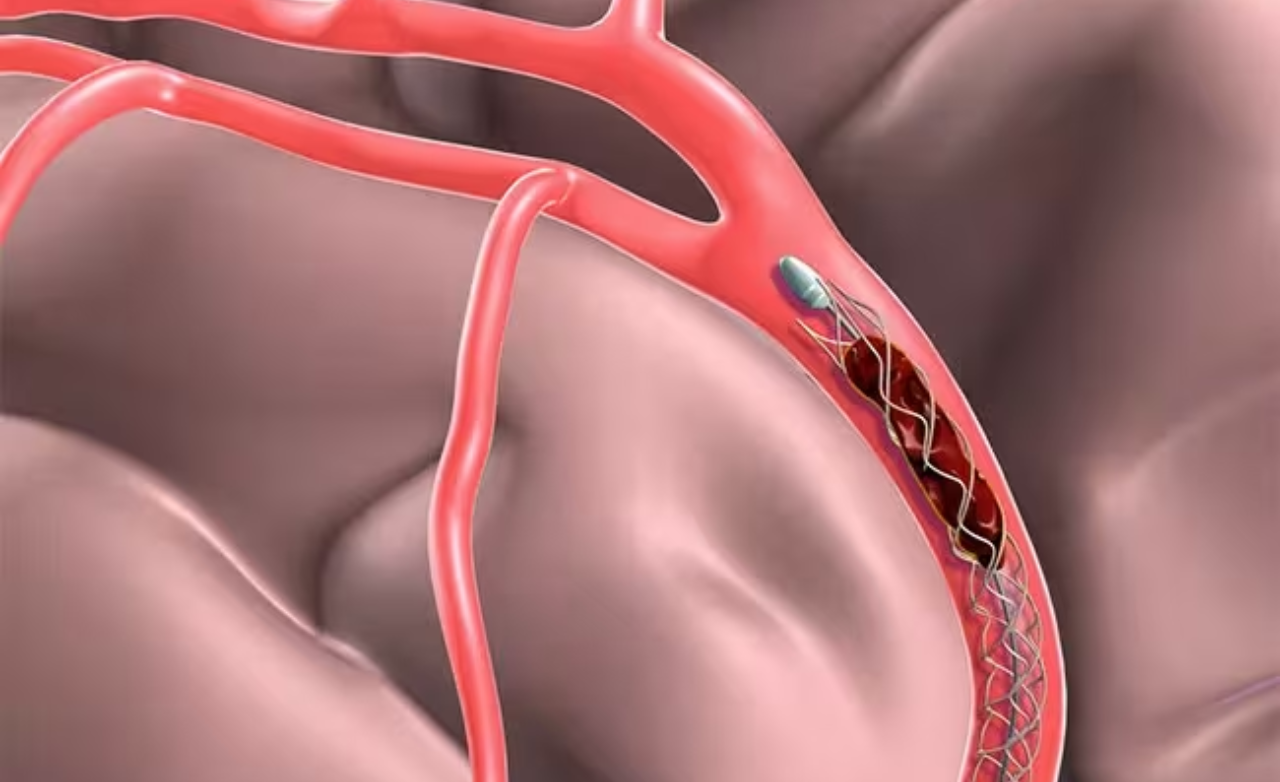

Minimally invasive technique using soft coils to block aneurysm flow, preventing rupture and ensuring long-term vascular stability.

Provides support for wide-neck aneurysms, ensuring secure coil placement and safer, more effective treatment.

Enhances treatment by redirecting blood flow away from the aneurysm, promoting gradual healing, improving vessel stability, and ensuring stronger, durable protection against future rupture.

Placed directly inside the aneurysm sac, these devices offer targeted treatment with minimal vessel manipulation for improved safety.